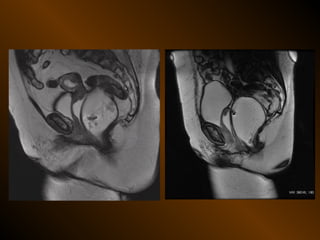

Cộng hưởng từ

QUANG MẠCH • Chỉđịnh giới hạn X QUANG CAN THIỆP Dẫn lưu áp xe bụng Thủ thuật nghẽn mạch cầm máu Dẫn lưu đường mật Mở túi mật ra da CÁC KHẢO SÁT KHÁC Cản quang ống tiêu hóa: baryt, tan trong nước Cộng hưởng từ CÁC KỸ THUẬT